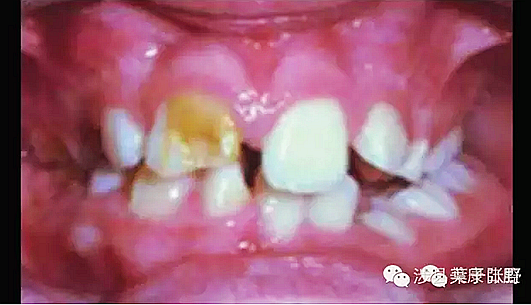

影響乳牙下方的恒牙胚。

WV8YN4A2K6RR`U_ZB29DZ~8.png

造成恒牙釉質(zhì)發(fā)育不良。